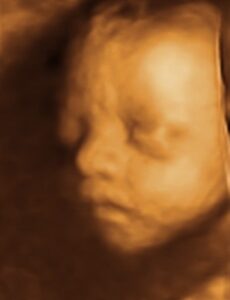

La ecografía 4D es mucho más que una imagen en movimiento: es una oportunidad única para conocer al bebé antes de su nacimiento y, al mismo tiempo, una herramienta médica avanzada que permite observar su desarrollo con gran precisión.

Gracias a la tecnología de alta resolución, podrás ver sus rasgos, sus movimientos e incluso sus gestos, viviendo una experiencia emocionante y cercana. Para el equipo médico, esta técnica ofrece una valiosa información sobre el bienestar fetal, la posición y el crecimiento del bebé, siempre con total seguridad para la madre y el futuro recién nacido.

Recomendamos realizar la ecografía 4D entre las semanas 26 y 32 de embarazo, el momento ideal para obtener las mejores imágenes.